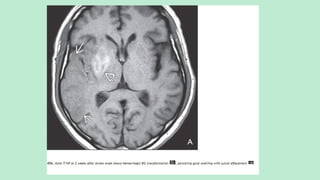

Procedure of choice: MR with DWI .T2/FLAIR scans show

round or ovoid hyperintensities in the medial thalami, just

lateral to the third ventricle.

In slightly more than half of all cases, aV-shaped hyperintensity

involves the medial surfaces of the cerebral peduncles and

rostral midbrain.

DWI shows diffusion restriction in the affected areas.